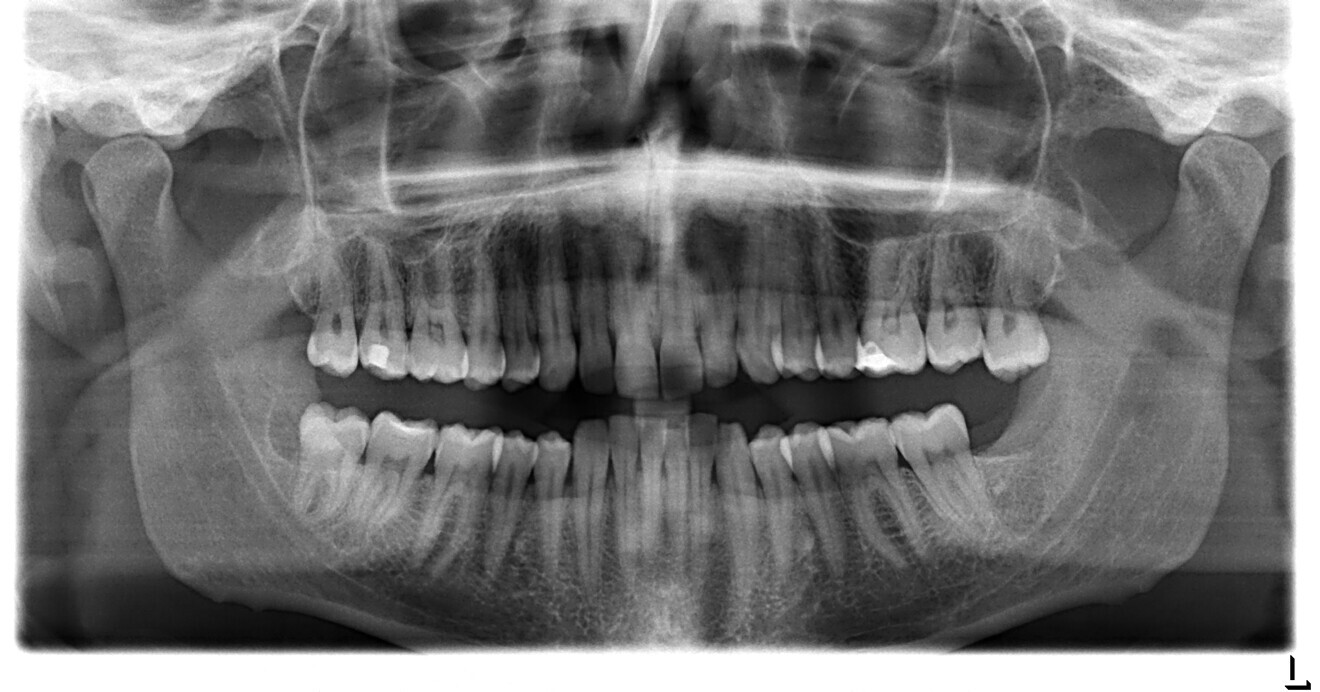

A 37-year-old male patient presented with the chief need for re establishing anterior alignment in both arches. Facial analysis showed a short face with a flat profile but proper chin projection (Figs. 9–12), and clinical examination revealed a skeletal Class I (ANB = 0.89°) and dental Class I malocclusion with severe deep bite (almost 100%), a deep curve of Spee, normal maxillary central incisor torque (Ui–FH = 110°), mild maxillary crowding and moderate mandibular crowding (Figs. 13–18). The deep bite components were represented in this patient by the severe skeletal condition of hypo divergent pattern (FMA = 14.24°) with normal maxillary and mandibular incisor inclination and decreased gonial angle (110.46°). Analysis of the cephalometric radiograph indicated a reduced lower anterior facial height, combined with a hypo-divergent pattern (Fig. 19). The only treatment option suggested was orthodontic treatment with aligners for deep bite correction with all the features described (bite ramps, pressure area, 3D curve of Spee levelling, Class II elastics and heavy occlusal contacts).

Fig. 13